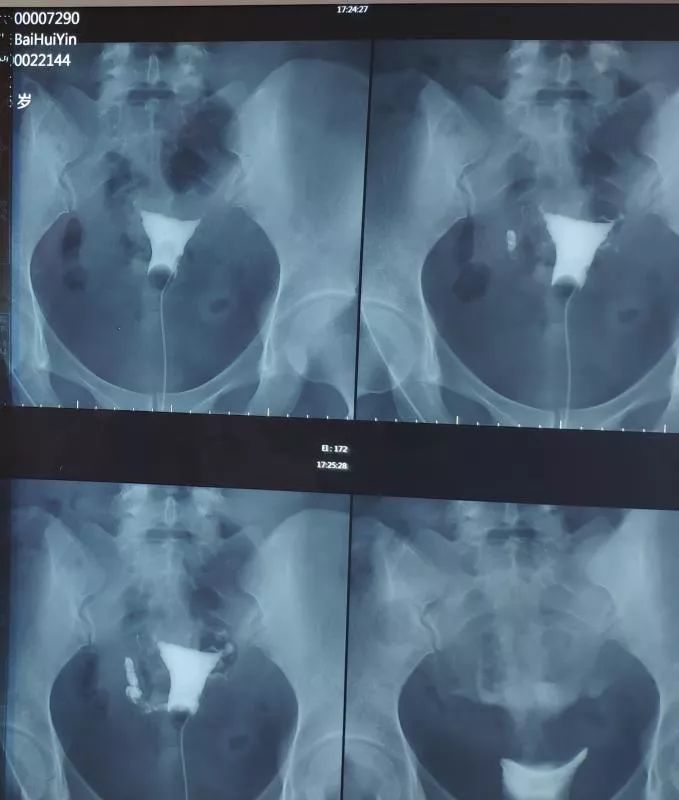

白女士,3月前因不孕症查子宫输卵管造影:输卵管双侧梗阻,少量造影剂弥散(即双侧输卵管不通)如下图: